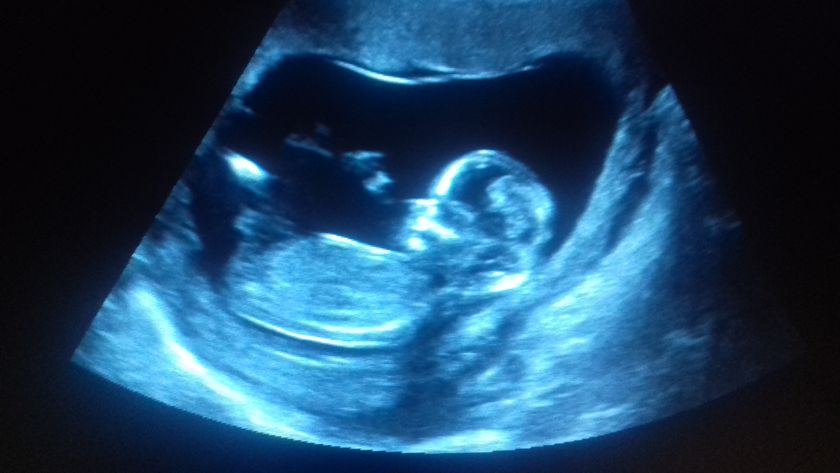

Балашихинский МОПЦ это, конечно, то еще заведение… Мне в поликлинике клялись, что очередей на скрининг давно нет (хотела просто платно пройти в Инвитро), поверила, пошла, просидела с 10.40 до 13.30 в очереди ? В коридорчике 15 кв м, куда поместилось еще 15 человек. Оставили синяк на руке, иголка, будто сапоги шить?В общем, больше не хочу туда ходить))) А так, подтвердили (пробубнили), что у нас все в срок и хорошо, и даже удалось фото с экрана сделать?

Ручкой машет, а вторая вроде за головкой! Поздравляю вас! Пол не предположили?

Спасибо) Да, так и есть про руки) А пол там не говорят. В инвитро предположили девочку, но это не точно на таком сроке)